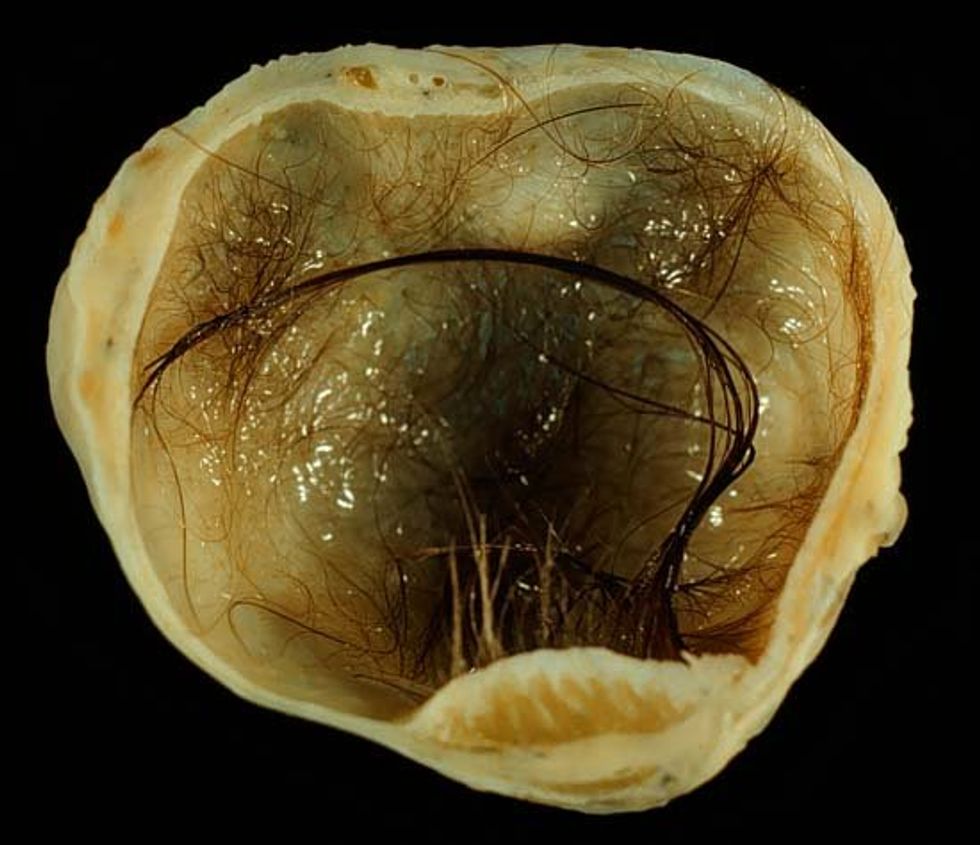

Mostly, people just wanted to know if they could see a picture of the actual teratoma. Stuthers did eventually show a photo briefly in a follow up video, but luckily for us, we can get a better look at these things through a plethora of high-res online images.

Ready? If you're squeamish, you might want to look away now.

When she woke up from the anesthesia, the doctors had news. Her mom was there to capture the moment Stuthers heard that what was removed from her body was no normal ovarian cyst. It was a teratoma—a unique kind of tumor that grows from germ cells (cells that eventually become sperm or, in Stuthers' case, eggs). Because of their origin, teratomas frequently grow hair and even teeth, along with various kinds of tissue. The teratoma inside Stuthers' ovary had all that, and more... The surgeons even thought Stuther's teratoma may have had an eyeball! (Later testing ruled this out... close call!)